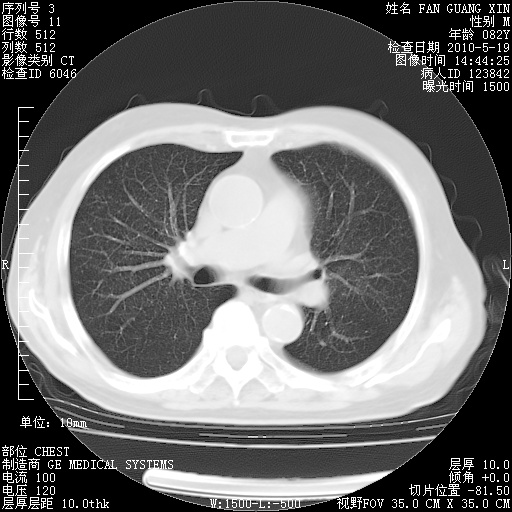

可改为口服强的松40-50mg/d治疗,若病情仍稳定,胸部阴影不再吸收可逐渐减量